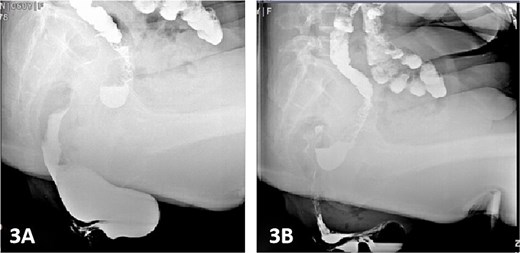

Colonic transit time assessment was performed using radiopaque markers. At 24 h post-ingestion, 19 markers were retained within the colon, with complete clearance observed at 48 and 72 h, confirming normal colonic motility (Fig. 2). Defecography demonstrated a Grade III RC, characterized by a maximal depth of 76 mm during straining and persistent barium retention post-evacuation, consistent with obstructed defecation syndrome (ODS) (Fig. 3).